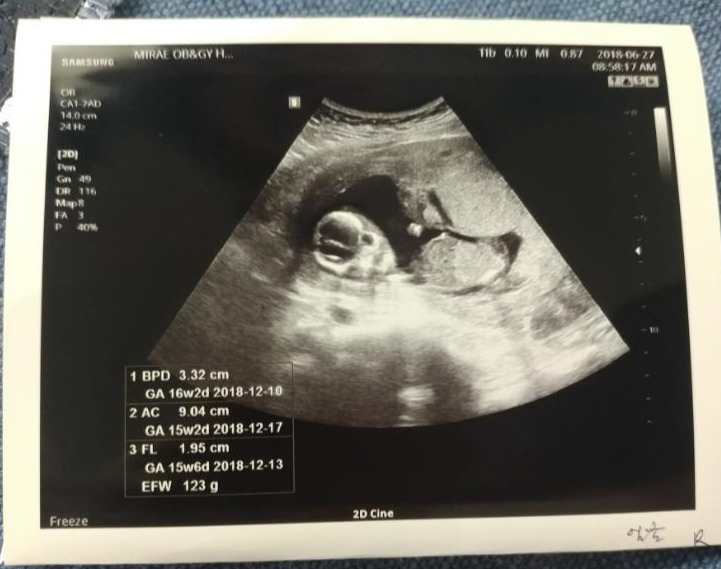

룰루&랄라. 랄라는 늘 초음파 카메라로 엄마를 또렷하게 쳐다본다. 룰루는 엄마가 TV볼 때처럼 항상 같은 자세로 눕방이다.